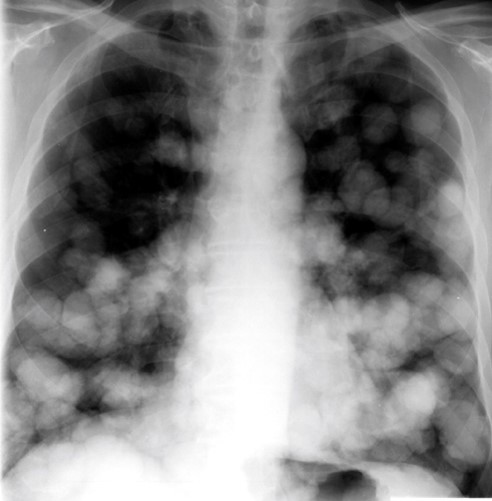

20yo with gradually increasing SOB & cough over 6 mo

View

DX

View: PA

DX: metastatic disease